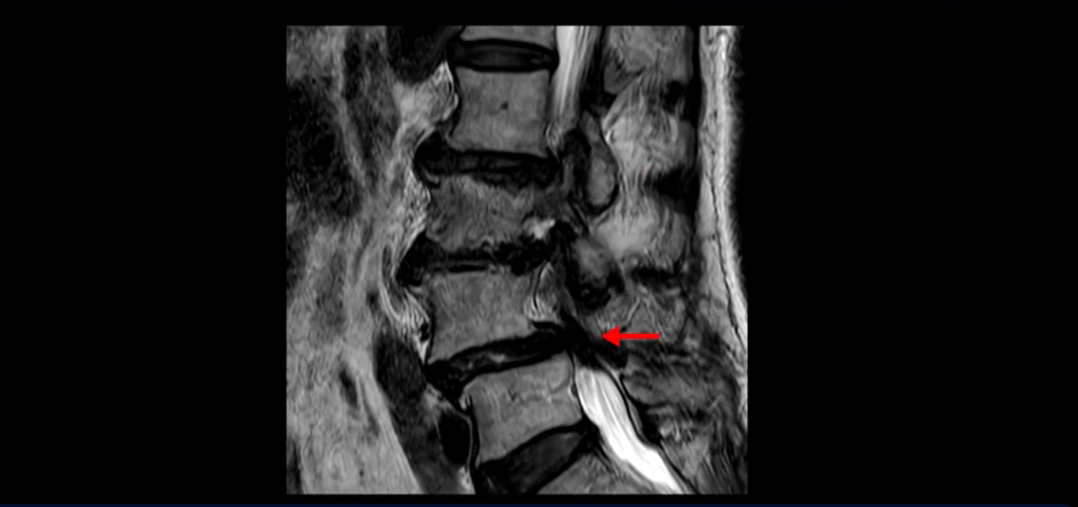

이분 MRI 보시면 허리 3마디의 퇴행이 매우 심합니다.

4번 5번에는 뼈가 밀려 나간 전방전위증도 있고,

또 척추관협착도 매우 심합니다.

척추관이 심하게 좁아져 있습니다.

이렇게 여러 마디가 안 좋고 뼈도 밀려 나가 있으니까 나사박는 수술해야 하는데, 대학병원에서도 수술을 한 번에 못 하고 두 번에 나눠서 해야 한다고 들으셨습니다. 왼쪽으로 신경가지가 빠져나가는 추간공도 많이 좁아져 있습니다.